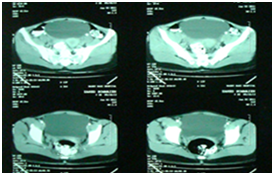

A 23 year-Old Iranian female patient presented with a six months history of fever, chest and abdominal pain, loss of appetite, weight loss, cough, night sweating and dyspnea was referred to our hospital. Physical examination revealed fever (39 centigrade), blood pressure 110/60 and coarse crackles at middle and lower area of both lungs. Abdomen was soft but a budging was seen in lower abdomen near the suprapubic region. Others organ, upper and lower extremity was normal. There was bilateral multiple nodular lesions at his chest X-ray. In hospital she takes ceftriaxone 2Gr and clindamycin 600mg twice daily. US of abdomen and pelvic was obtained and showed a cystic–solid lesion in the pelvic and in the liver. Computed tomography (CT) scan of the chest, abdomen and pelvic with IV contrast was obtained and showed multiple cavitary and solid-cystic mass lesions was showed in both lungs and the size of lesions were various in diameter. The lesions were located in the central and peripheral zone of both lungs (Figure 1). The abdomen and pelvic CT–scan showed solid-cystic mass in the pelvic and liver Radiologist finding and differential diagnosis was inflammatory lesion as Wegener granuloma, septic emboli, sarcoidosis and pulmonary metastasis from ovarian malignancy (Figure 2). Two days after admission, fever dropped and general condition of the patient becomes better. All lab date was normal except (ESR=40(0–20mm/h.CRP=22(0–5mg/L), WBC=16000). Fibroptic bronchoscopy was performed. Endobronchial lesion was not observed and bronchial lavage was obtained, Pathology examination of the bronchial lavage was normal, all other biochemical tests (CEA, ACE, RF, CA-125, hydatid tests and rheumatological tests) were normal. Laparatomy was performed ,the pelvic mass was excised and mass was opened, laminated membrane of hydatid cyst was seen, the lesion of liver was aspirated and fluid was clear, the mass was opened carefully and laminated membrane was seen (Figure 3) (Figure 4). With left mini anterolateral thoracotomy at 4 thintercostal space, chest wall was opened multiple nodules was palpable the big one was resected as wedge resection, the specimen was opened, laminated membrane was exposed (Figure 5). Chest tube was inserted and chest wall was closed in layers. Second post operative day, Albendazole was started at a dose of 10mg/kg/day for three cycle of 28days with 14days interval. Pathologist’s repot was hydatid cyst of lung in all three specimens (Figure 5). Patient was discharged in good condition 5days postoperative in the six months follow -up time there was no increased the size of both pulmonary nodules.

Figure 2 CT –scan of pelvic show cystic –solid lesion mass.

During the growth , the cysts of lung may rupture in the tracheobronchial system or pleural space and patients complain of cough, expectoration of membranes, dyspnea, hemoptysis, and chest wall pain.1‒4 But in most uncomplicated cases of lung cysts are incidental finding or the patient may presents with dry cough, dyspnea, and chest pain.2‒4,8 The most common complication of pulmonary hydatid cyst is a secondary bacterial infection.2‒4,8 Infection resulting difficulty in differentiation it from an abscess or neoplasm lesions.3,4 Our case presented with fever, productive cough, dyspnea, chest pain and night sweating and this clinical presentation of our case mimicked a pulmonary infection such as tuberculosis or pulmonary abscess or pulmonary metastasis. Pelvic ultrasound has a low cost and a high sensitivity and constitutes the method of choice for pelvic and liver hydatid cysts.2,3,9 Pelvic and abdominal computed tomography allows to show the features, anatomic localization and extension of cystic masses. Pelvic magnetic resonance imaging (MRI) may be useful to recognize differential diagnosis of some tumor lesion in pelvic which including myxoid tumor such as myxoidneurofibroma and angiomyxoma(tun), Chest radiographs are useful to detect associated pulmonary hydatid cyst.9,10 In our case, pelvic hydatid cyst diagnosis was suggested by ultrasound CT-scan. In our case, hydatid serology test was not performed .The optimal treatment of pelvic hydatid cyst remains surgery. In our case we performed a diagnostic laparotomy, during exploration, we find a cystic–solid lesion of ovarian, after aspiration and evacuation, laminated membrane of hydatid cyst presented, lesion on the liver was aspirated, evacuated, hydatid cyst membrane was presented. With a mini thoracotomy a wedge resection of left lung was performed, daughter cyst and laminated membrane was presented from this lesion. The definitive diagnosis obtained from pathologist in all three specimens. Postoperatively, Albendazole was started at a dose of 10 mg/kg/day for three cycles of 28days with 14days interval. Patient was discharged in good condition 5days postoperative in the six months follow-up time there was no increased the size of both pulmonary nodules.